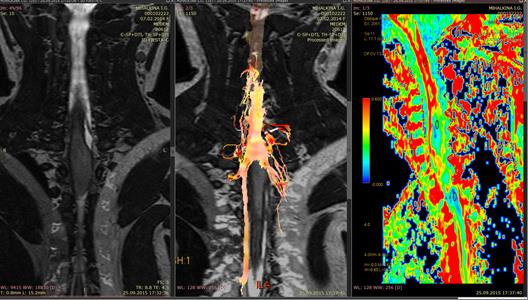

(рус) Злокачественные опухоли спинного мозга